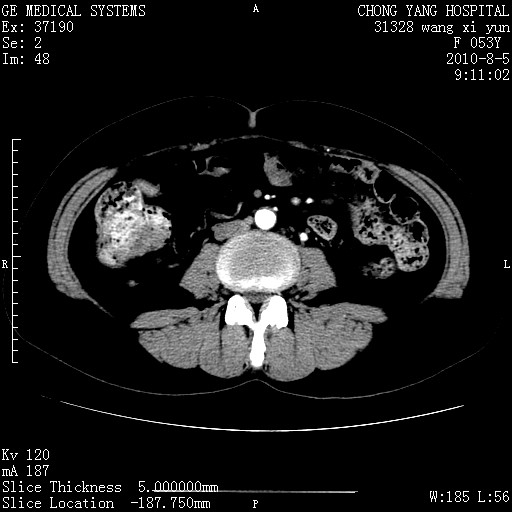

标题: CT28214:F41Y 血尿二十天,建议盆腔平扫加增强。

1)考虑肝左叶胆管细胞癌。2)脂肪肝。

支持胆管细胞ca。